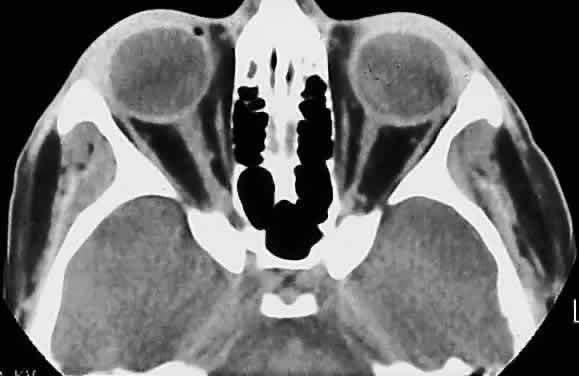

The optic nerve is affected in some manner in 1% to 5% of patients with sarcoidosis and is the second most frequently involved cranial nerve—the facial nerve being the most common.67,68 Rarely, sarcoidosis may present as tumefactive enlargement of the optic nerve without evidence of systemic disease. Most cases are misdiagnosed initially as meningioma or orbital pseudotumor (Figs. 50 and 51).67,69

Fig. 50. Bilateral thickening of the optic nerve and sheaths due to sarcoidosis. Computed tomography.

Fig. 51. Sarcoidosis of the optic nerve. Noncaseating granulomas replace the optic nerve parenchyma (low power, left; high power, right).